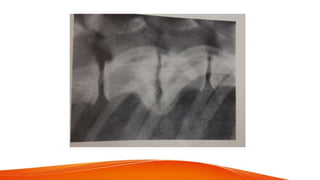

• Radiographic signs - narrowing of IVD space

narrowing & cloudiness of intervertebral foramen

abnormal spacing of articular process

presence of mineralized mass above IVD space